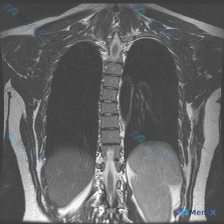

整理到一个很有意思的影像读片材料: 一张胸部MRI-T2序列冠状位影像,原始的影像学分析写的是“胸廓、脊柱、纵隔及肺野解剖结构基本正常,未见明显的病理性高信号改变”,甚至明确提了“椎体信号均匀,骨皮质轮廓清晰,未见明显骨质破坏”。 但拿到这份材料的人,第一眼观察到的线索是——脊柱侧弯(Scolios...

整理到一份临床诉求指向「脊柱侧弯」的病例资料: 仅有的影像检查是胸部MRI冠状位T2加权像,影像报告的核心发现是: - 双侧肺野、纵隔、心影未见明显局灶性病变或占位; - 胸椎序列清晰,椎体形态基本正常,未见明显的形态异常或骨质信号改变; - 双侧胸廓、软组织结构大致对称。 但结合「脊柱侧弯」的核心...

整理到一个挺有意思的病例复盘点,想跟大家讨论下临床思维: - 核心场景:患者主诉“脊柱侧弯”,但拿到的一张胸部冠状位T2 MRI报告里写着「胸椎序列排列整齐,左右基本对称,未见明显异常」。 - 影像背景:图像清晰度良好,胸廓、肺野、上腹部显露部分确实没看到积液、肿块或骨髓水肿信号。 问题来了:这种主...